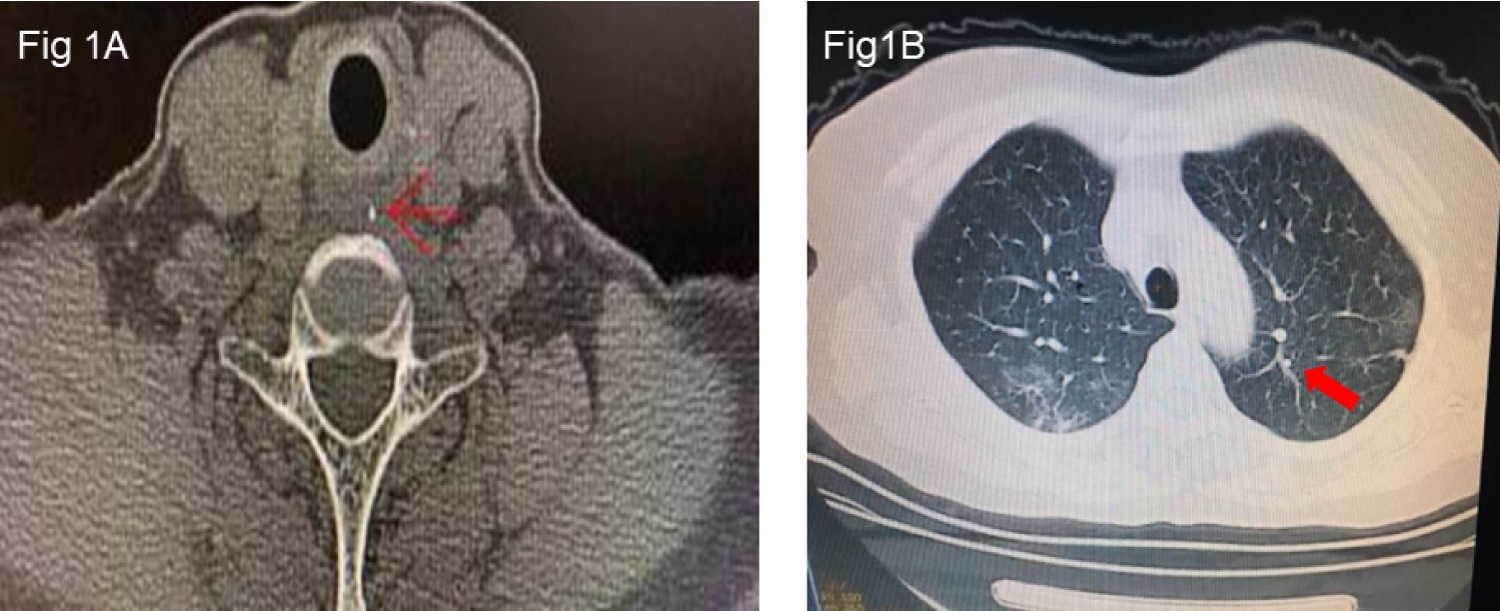

A diagnosis of foreign matter ingestion was confirmed by chest computed tomography (CT), which showed an ingested fishbone in the upper esophagus (Figure 1A). Pertinent laboratory results showed lymphocyte 1.01 G·L-1, lymphocyte ratio 18.6%, and C-reactive protein 38.42 mg·L-1. Other biochemical and coagulation parameters were within normal limits. The SARS-CoV-2 detected in oropharyngeal swab samples was positive by real-time reverse transcription-polymerase chain reaction (RT-PCR) assay, whereas other viral respiratory pathogens were all negative. Chest CT showed bilateral ground-glass opacities of peripheral lungs, which are the typical manifestations of COVID-19 (Figure 1B).

Figure 1: 1A: Foreign matter in the upper esophagus located at the position equivalent to the 7th cervical spine. Red arrows represent fishbone foreign matter. 1B: Chest CT images showed ground-glasslike shadows and patchy consolidation of bilateral lung fields.